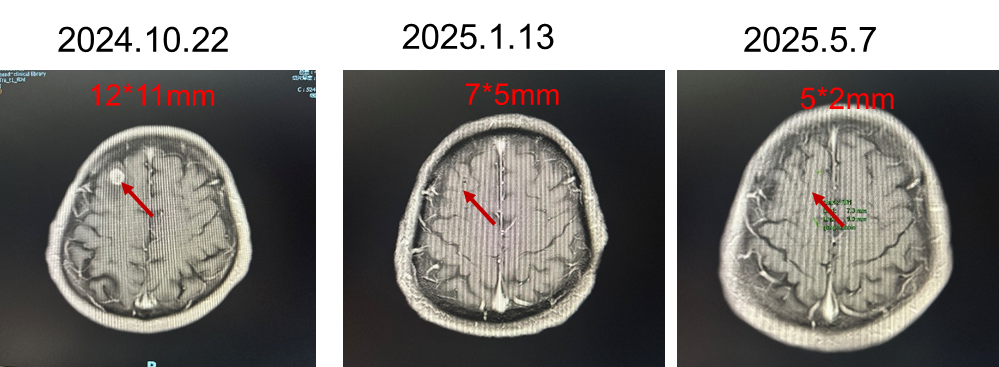

头颅增强MRI(2024-10-22)示:1.右侧额叶结节,考虑转移瘤伴瘤周水肿;2.双侧额顶叶及侧脑室周围多发异常信号影,考虑脱髓鞘改变。

2024年10月9日开始给予长春瑞滨软胶囊100mg d1,8+奈达铂60mg d1-2+血管内皮抑制素75mg d1-2,60mg d3治疗5周期;后因血小板减低,行长春瑞滨软胶囊40mg tiw节拍化疗+血管内皮抑制素75mg d1-2,60mg d3维持治疗3周期。并于2024-11-06行脑转移瘤射波刀治疗1次。

治疗过程中的影像学变化: